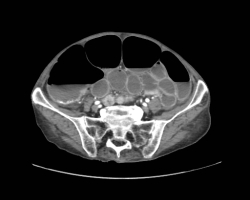

L’arthrose de hanche ou coxarthrose est une maladie fréquente, consistant en une lésion de l’articulation de la hanche, cartilage et os, d’origine mécanique. […]